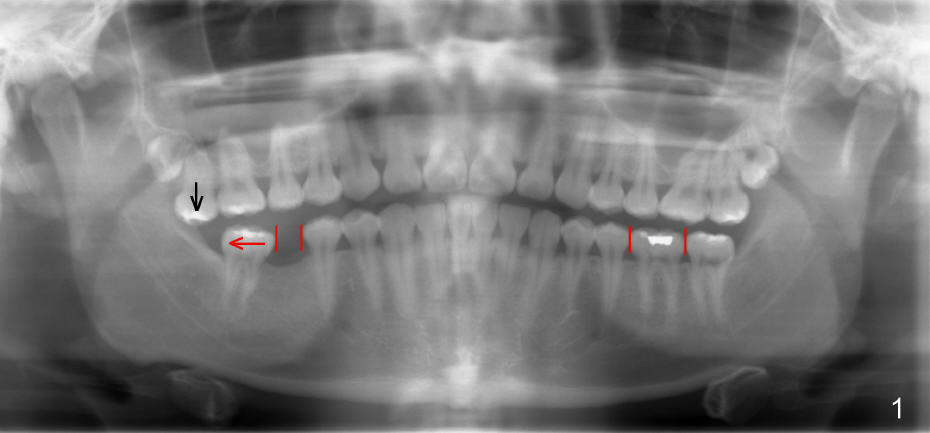

Twenty-year-old man requests restoring missing tooth #30 (Fig.1), but the edentulous space (red lines) is narrow as compared to the mesiodistal width of #19. Ideal treatment plan is to distalize #31 (red arrow) with mini-implant (mini in short) and restore the missing tooth with traditional implant.

For 10 months, there is no sign of movement in spite of the effort to tackle supraeruption of #2 (Fig1. black arrow). First, composite is placed on occlusal surface of the left molars for several occasions. It is worn off quickly. Incisal guidance is made. Probably the kid does not wear it constantly. Occlusal reduction is also tried for #2.

The tooth #31 is uprighted in six months (Fig.8, as compared to Fig.5). The edentulous space increases from 6 mm to 9 mm mesiodistally, which is still not enough. The M-D width of #19 is 12 mm. In fact, the tooth #2 has been intruded substantially (Fig.9. Compare to Fig.3). The possible reason for resistance of distal movement of #31 is an interference from the tooth #3 (Fig.10). A regular implant is placed intentionally in the distal aspect of the edentulous area (Fig.11: I). The next plan is to place temporary crown on the implant once it osteointegrates to raise the occlusion efficiently so that the tooth #31 is free to move distally with retraction of power chain attached to the mini-implant (as shown in Fig.2). The regular implant may be also used as anchorage to push #31 distally. See you later.